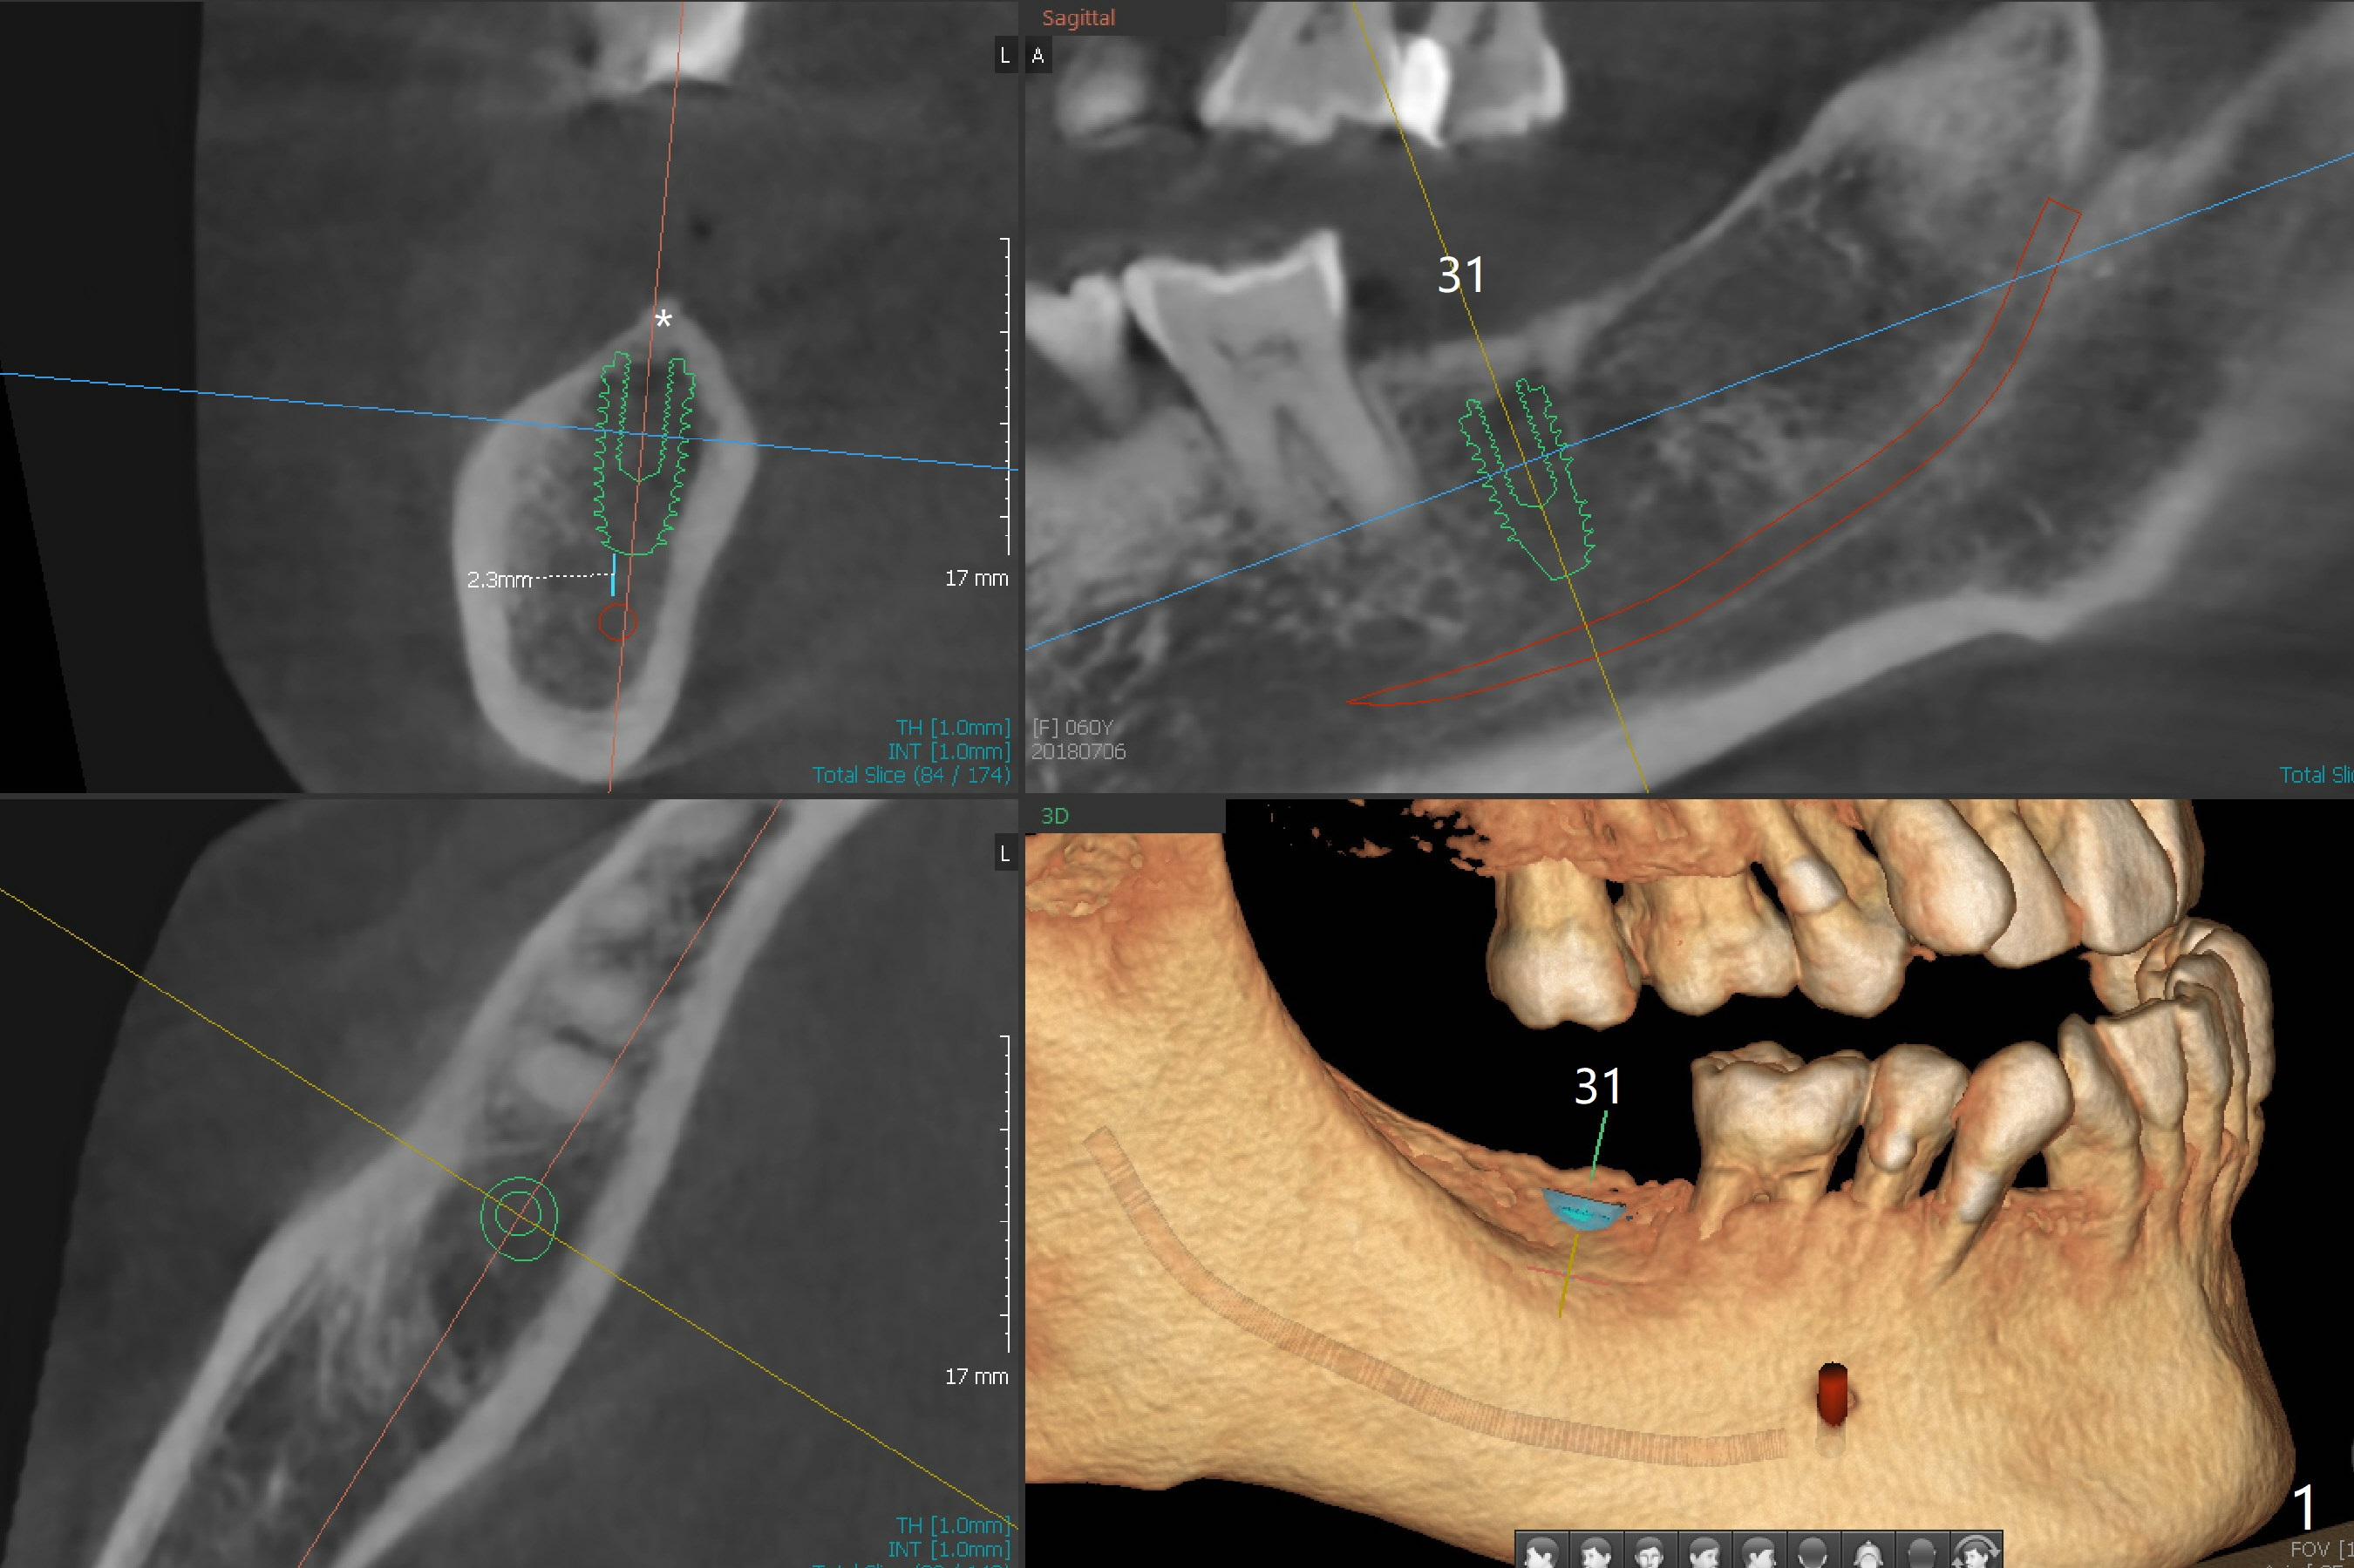

A 60-year-old woman requests implant to replace a missing tooth at #31 (Fig.1). The crest is pointed (Fig.1,2 *). It will be flattened with bone trimmer before pointed drill.